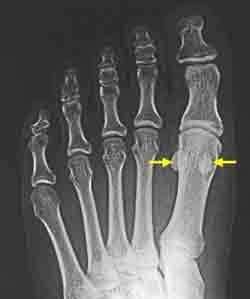

大腳趾的下方出現老繭和疼痛,嚴重時影響行走,多見於拇趾外翻和喜歡穿高跟鞋的人。修腳師和皮膚科醫生最常見到,這些老繭雖然可以削除,但很快又會長出來。按壓這個部位會有疼痛感,有時會出現腫脹。原來老繭的裡面存在兩塊籽骨,是這兩塊籽骨在作怪。

籽骨:位於肌肉止點處腱與骨之間,是由肌腱骨化形成的。能夠改變肌腱抵止的角度,加大肌肉的力壁,增大肌肉拉力。妊娠期8周在拇短屈肌腱中能確定籽骨,胎兒期12周籽骨軟骨化,8歲開始骨化,直到12歲。腓側籽骨先於脛側籽骨骨化,女性先於男性。籽骨包裹於拇短屈肌兩頭、拇展肌肌腱與拇內收肌腱內,拇長屈肌腱從兩枚籽骨間穿過,止於遠節趾骨的腹側基底部。籽骨與跖骨跖側面構成滑膜關節,關節面復蓋透明軟骨,脛腓側籽骨被籽骨嵴分開,平均矢狀面長12mm、冠狀面8mm,脛側籽骨比腓側大,腓側籽骨則相對較圓。籽骨由籽骨間韌帶、籽骨趾骨短韌帶與內外側籽骨韌帶固定於關節囊。籽骨的血供大部分由近端第一跖骨動脈經拇短屈肌腱由跖側面呈樹枝樣分叉進入籽骨,少部分來自遠端關節囊。